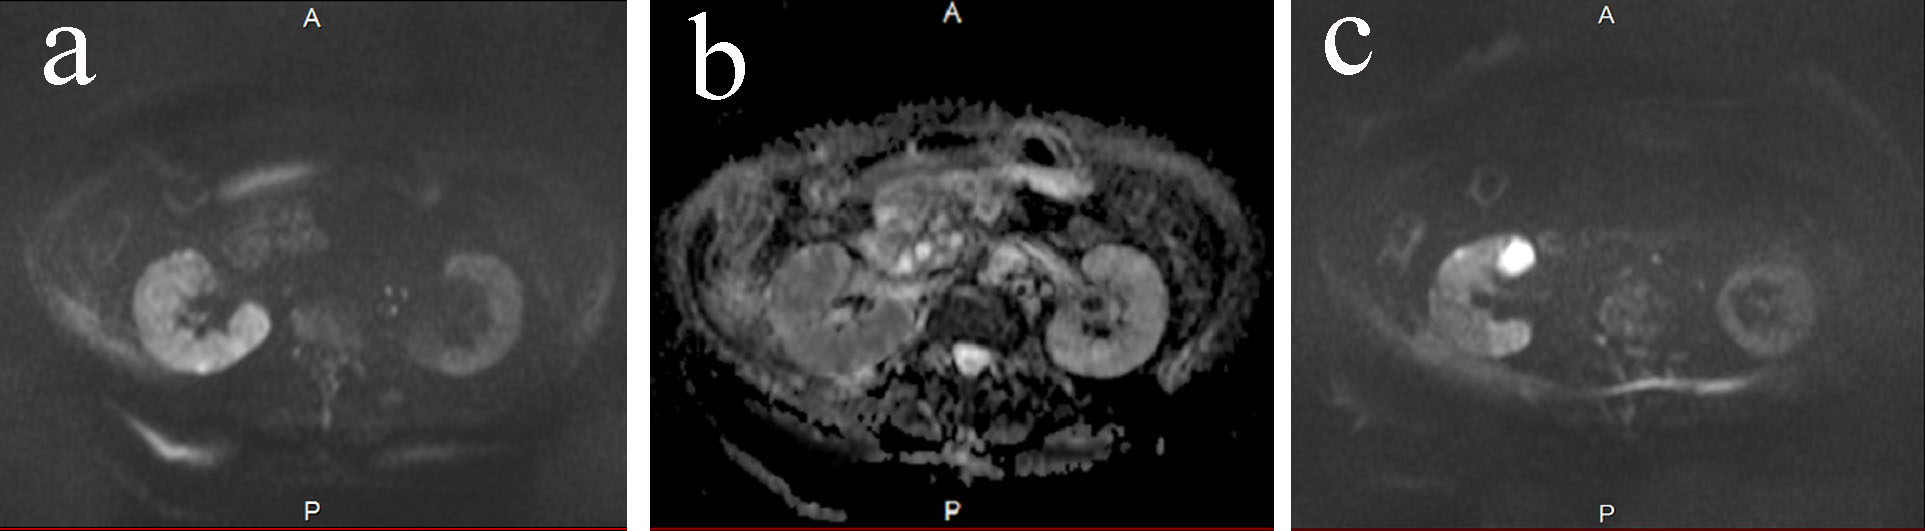

On admission, body temperature was 35.6 °C, and other vital signs were normal. She did not show fever before admission. Physical examination did not show abnormal signs of the abdomen and costovertebral angle tenderness. Blood examination demonstrated elevation of aspartate aminotransferase (AST) at 80 U/L, alanine aminotransferase (ALT) 47 U/L, alkaline phosphatase (ALP) 553 IU/L and γ-glutamyltranspeptitase (γ-GTP) 140 IU/L. Total bilirubin (0.5 mg/dL) was within normal limit. Leucocyte count was 13.5 × 109/L, and C-reactive protein was 26.8 mg/dL, which was remarkably high. Urinalysis showed slightly elevated number of leukocyte, which was 5 - 9 per high power field. Ultrasonography demonstrated enlargement of the gallbladder and dilatation of the bile duct, but the gallbladder wall was not thick. Right renal pelvis was slightly dilated, and right renal cortex seemed edematous. Contrast-enhanced CT also showed enlargement of the gallbladder and dilatation of the bile duct, but did not reveal any biliary stone or tumor that could have caused obstruction. CT also showed slightly swollen right kidney. It was difficult to differentiate UTI and cholangitis. If the diagnosis was cholangitis, biliary drainage was necessary. We first started to use sulbactam/ampicillin 3 g every 8 h to treat both possible diseases. DWMRI exhibited high signal intensity, and apparent diffusion coefficient (ADC) showed low signal intensity on the right renal pelvis compared with the left one (Fig. 1a, b), suggesting the existence of pyelonephritis. DWMRI also revealed high intensity in one of the cysts in the right kidney, which indicated renal cyst infection (Fig. 1c). After a few days, E. coli was isolated in culture of the blood and urine, and the urinary bacteria were 104 colony forming unit (CFU)/mL. We diagnosed as UTI, and changed the antibacterial treatment to cefazolin according to the diagnosis of UTI and drug susceptibility. Cyst drainage was an option, but since she made good progress with the antibiotic treatment alone, we did not conduct cyst drainage. Serum levels of AST, ALT, ALP and γ-GTP decreased, and bile duct dilatation disappeared, and then she was discharged from the hospital. DWMRI was performed over two times for follow-up, which showed low intensity of the parenchyma and cyst, suggesting that the pyelonephritis and cyst infection was well treated with antibiotics (Fig. 2). DWMRI after the treatment demonstrated significantly reduced intensity of renal parenchyma and cyst, confirming the usefulness of DWMRI for diagnosis of pyelonephritis and renal cyst infection.

![]() Click for large image | Figure 1. (a) DWMRI on day 0. The high signal intensity was seen in the right kidney. The intensity was apparently higher than the left kidney. (b) ADC map on day 0. The intensity was low in the right kidney. (c) DWMRI on day 0. One of the cyst showed high intensity. |